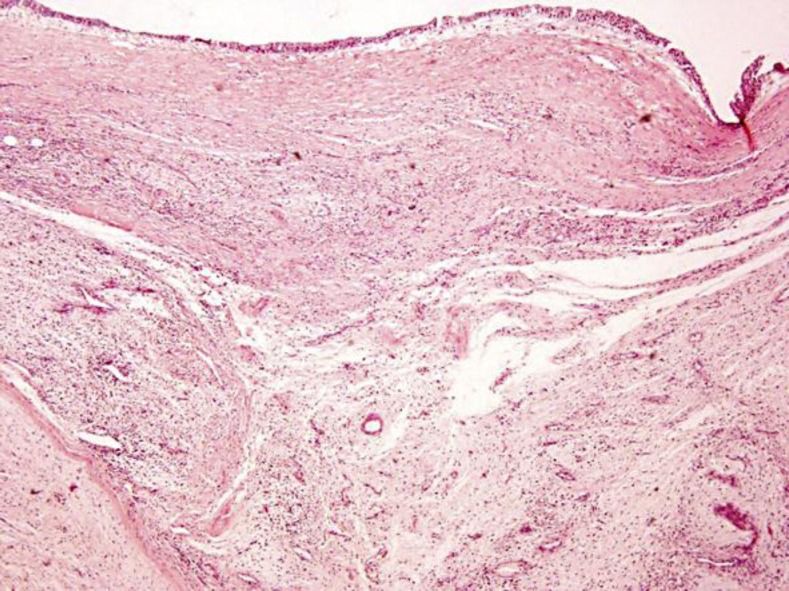

发生在泌尿生殖系统的肉瘤十分罕见,约占所有软组织肉瘤的2.1%,预后较差。肾肉瘤相当罕见,约占恶性肾病例的1-3%。肾脏低级别纤维黏液样肉瘤(LGFS)是一种非常罕见的,惰性但转移的软组织肉瘤,具有看似良性的组织学特征。估计5年总生存率超过90%,但可能发生很晚的局部复发和远处转移,这强调了长期随访的必要性。我们报告一例48岁男性患者的LGFS位于肾盂。这可能是第一次报道起源于肾盂的LGFS。

Sarcomas of the genitourinary tract are quite rare, accounting for 2.1% of all soft tissue sarcomas and have a poor prognosis. Kidney sarcomas are quite rare, representing 1–3% of malignant renal cases. Low-grade fibromyxoid sarcoma (LGFS) of the kidney is an exceedingly uncommon, indolent but metastasizing soft tissue sarcoma with deceptively benign-appearing histological features. The estimated 5-year overall survival seems to be over 90%, but very late local relapses and distant metastasis may occur, which underlines the need for a long-term follow-up. We present a case of a 48-year-old male patient with a LGFS located on the renal pelvis. This is probably the first report of LGFS arising from the renal pelvis.